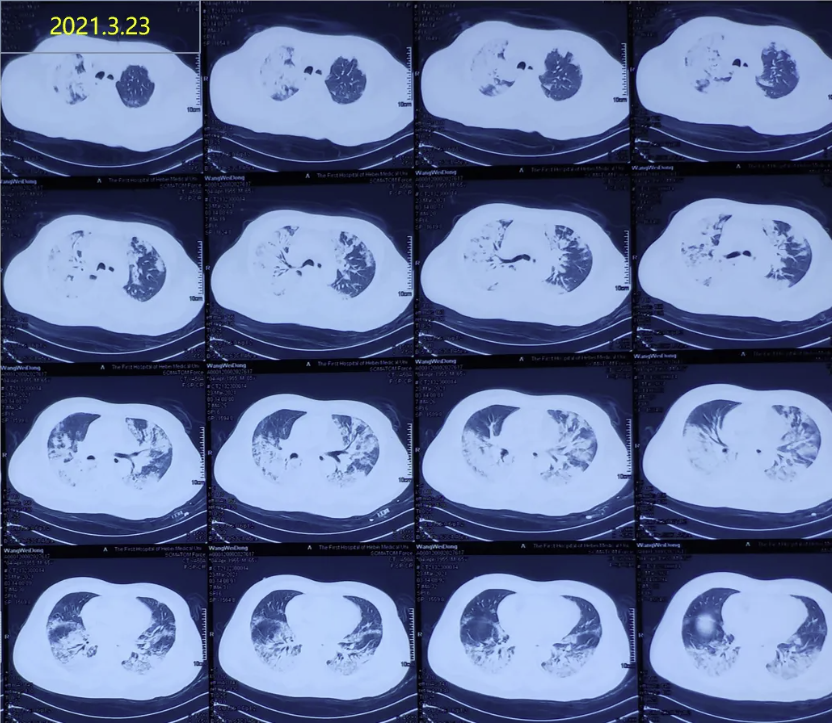

这是一名66岁男性患者的胸部CT对比,患者无明显诱因发热1月余,伴寒战,活动后呼吸困难加重,抗感染治疗效果不佳。

肺CT示双肺多发片状高密度影

5天前,氧合指数降至64.5mmHg,建VV-ECMO后收入RICU。